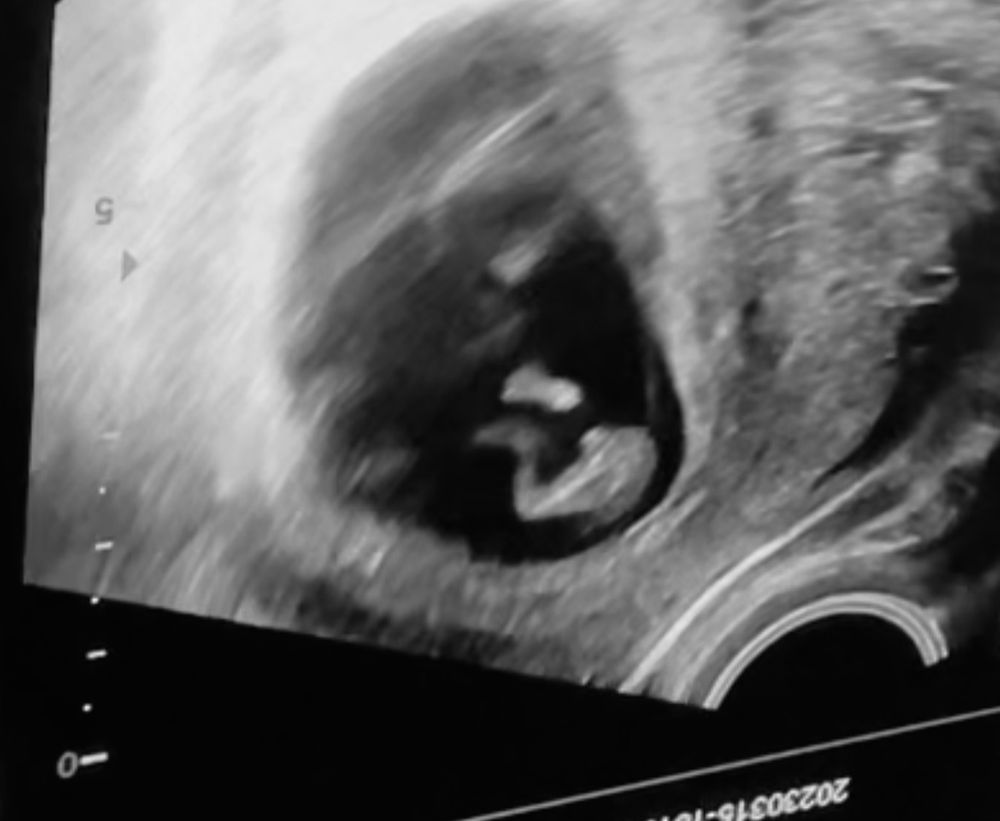

Итак моя история - В 10 недель я пошла на узи из за выделений чтоб убедится что все хорошо. И узист сказал сам, я даже не спрашивала, говорит у вас мальчик 100%. Можете покупать вещички говорит. Потом пошла на узи в 15 недель (фото прикладываю) и там вроде мальчик но узист ни чего не сказал. И кровь я сдала в тот же день в 15 недель и результат пришел У хромосома не выявлена пол плода женский.

На фото вроде явно пацан. Или я уже сума сошла?? 😂😂